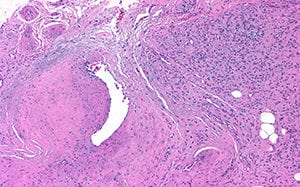

El informe histopatológico, reveló microscópicamente la presencia de una lesión polipoidea revestida de epitelio escamoso sin atipias y subyacentemente ocupando la totalidad del corion una proliferación difusa sin formación de plexos , constituida por células de citoplasma mal definido y bordes mal delimitados que contienen unos núcleos pequeños ondulados y con proliferación fibrilar, siendo el diagnóstico de neurofibroma solitario (Figura 6-8).